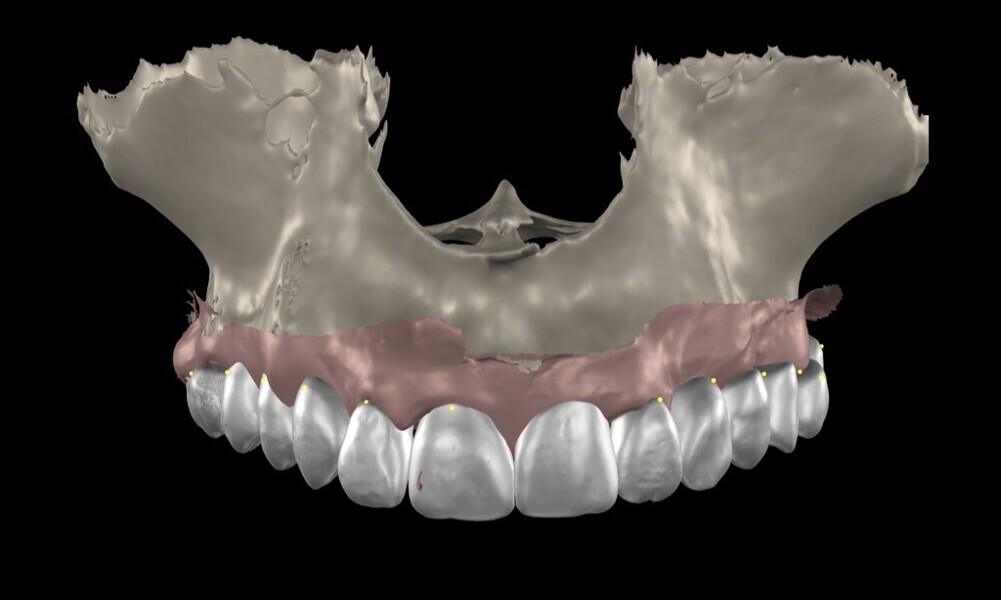

To ensure precise and predictable treatment planning, the DICOM files, STL files and clinical photographs were seamlessly integrated into Smilecloud, utilising advanced artificial intelligence technologies to deliver a highly personalised smile with exceptional precision (Figs. 11–15).

Figs. 11–15: DICOM files, STL files and clinical photographs were integrated into Smilecloud, leveraging artificial intelligence for precise, personalised smile design.